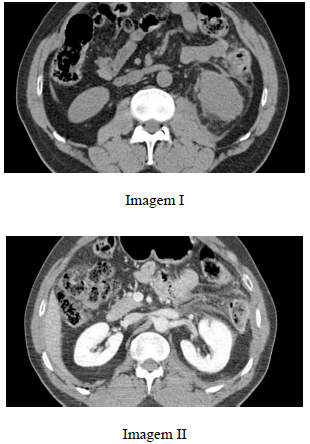

Paciente do sexo masculino, com 37 anos de idade, após cair de uma árvore de 6 m de altura, refere dor lombar à esquerda e hematúria. Realizou tomografia computadorizada de abdome, que evidenciou as imagens I e II a seguir.

Com base nesse caso clínico, julgue o item subsecutivo.

Observa-se isquemia do rim esquerdo, provavelmente relacionada à avulsão da artéria renal correspondente.